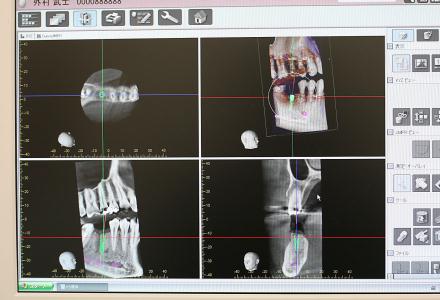

CTスキャンで撮影した画像は、瞬時に各ユニットのPCにデータが搬送され、即座にビュアー・ソフトを使い360°どの角度からも状態を見ることができます。

CTスキャン1台でパノラマ撮影、セファロ撮影、3D撮影が可能です。

最先端のデジタルテクノロジーを駆使し、より少ないX線照射線量で高品質画像が得られる3D画像のためのパノラマX線装置のため、様々な治療の診査に有効に利用しています。

CTスキャンの立体画像は、主にインプラントを含む口腔外科分野に威力を発揮しますが、断層方式パノラマX線写真や口内法X線撮影法では判別できない、痛みや症状の原因の究明にも役立っています。